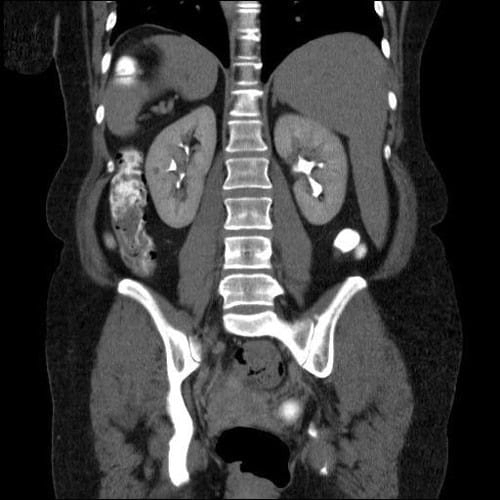

МСКТ брюшной полости с контрастированием

Мультиспиральная (многосрезовая) компьютерная томография – наиболее информативная диагностическая процедура, обеспечивающая врачей сведениями о состоянии органов и тканей пациента. МСКТ брюшной полости выполняется с контрастом, представляющим собой йодсодержащий раствор. Его накопление в очагах патологий позволяет визуализировать их под действием лучей сканера-томографа. Принцип действия установки основан на различной плотности и проводимости внутренних тканей человеческого тела.

Рассматриваемое исследование выполняется после прохождения пациентом УЗИ и классической пленочной рентгенографии. Томография позволяет уточнить размер и локализацию обнаруженных ранее патологий и выявить их характер. На основании полученных данных врачи могут поставить пациенту окончательный диагноз и дифференцировать заболевание от поражений организма со схожей симптоматикой.

Что показывает МСКТ брюшной полости

Сканирующие диагностические процедуры выполняются в двух случаях: для поиска патологических изменений в органах или контроля результатов проведенной терапии и радикального лечения. Исследование позволяет обнаружить:

• абсцессы;

• опухоли и иные новообразования;

• травмы и их осложнения;

• накопление экссудата в полостях.

Высокая разрешающая способность сканера обеспечивает врачей возможностью масштабирования отдельных участков сканируемого органа в режиме реального времени. Достоинством мультиспирального метода становится способность оборудования к одновременному исследованию паренхиматозных (не имеющих внутренних полостей) и полых органов человека.